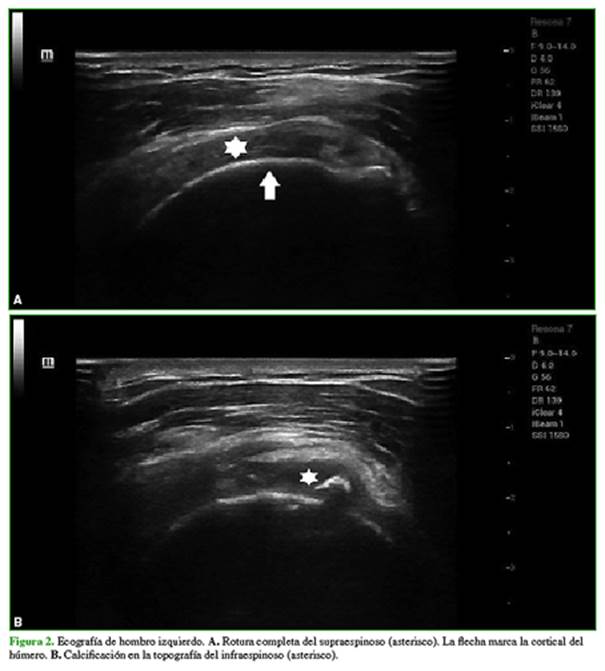

En el examen físico, no se palpan tumoraciones. Tanto la movilidad pasiva y como la activa están disminuidas y las pruebas para manguito rotador son positivas. Se solicitan una radiografía de hombro izquierdo en rotación interna y externa (Figura 1) y una ecografía de hombro (Figura 2).

HallazgoS e interpretación de los estudios por imágenes